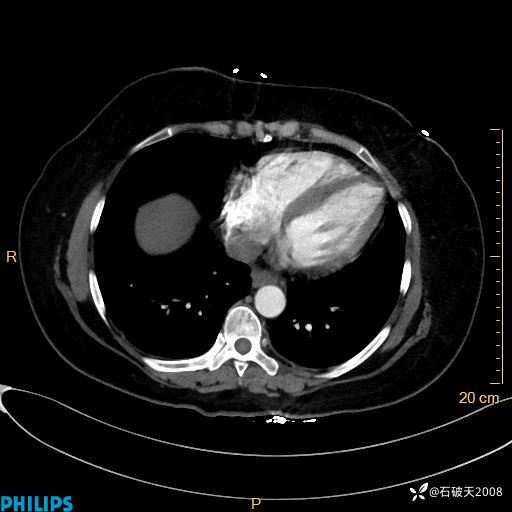

肺窗

纵隔窗